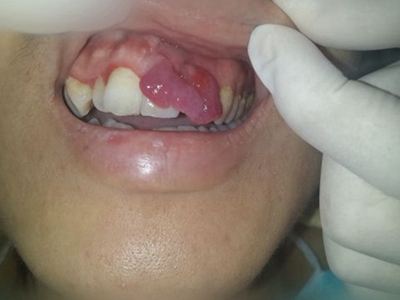

牙龈瘤是指发生在龈乳头部位的炎症反应性瘤样增生物,好发于女性,前磨牙区最为常见。牙龈瘤来源于牙周膜及牙龈的结缔组织,因其无肿瘤的生物学特征和结构,故非真性肿瘤,但切除后易复发,因此切除务必彻底,必要时拔除相关牙齿。

牙龈瘤多发于女性,以青年及中年人为常见,多发生于牙龈乳头部,位于唇、颊侧者较舌、腭侧者多,最常见的部位是前磨牙区。肿块较局限,呈圆形或椭圆形,有时呈分叶状,大小不一,直径由几毫米至数厘米。

肿块有的有蒂,如息肉状;有的无蒂,基底宽广,生长较慢,但在女性妊娠期间可能迅速增大。较大的肿块可以遮盖一部分牙及牙槽突,表面可见牙压痕,易被咬伤而发生溃疡,伴发感染。随着肿块的增长,牙槽骨壁逐渐被破坏,牙可能发生松动、移位。